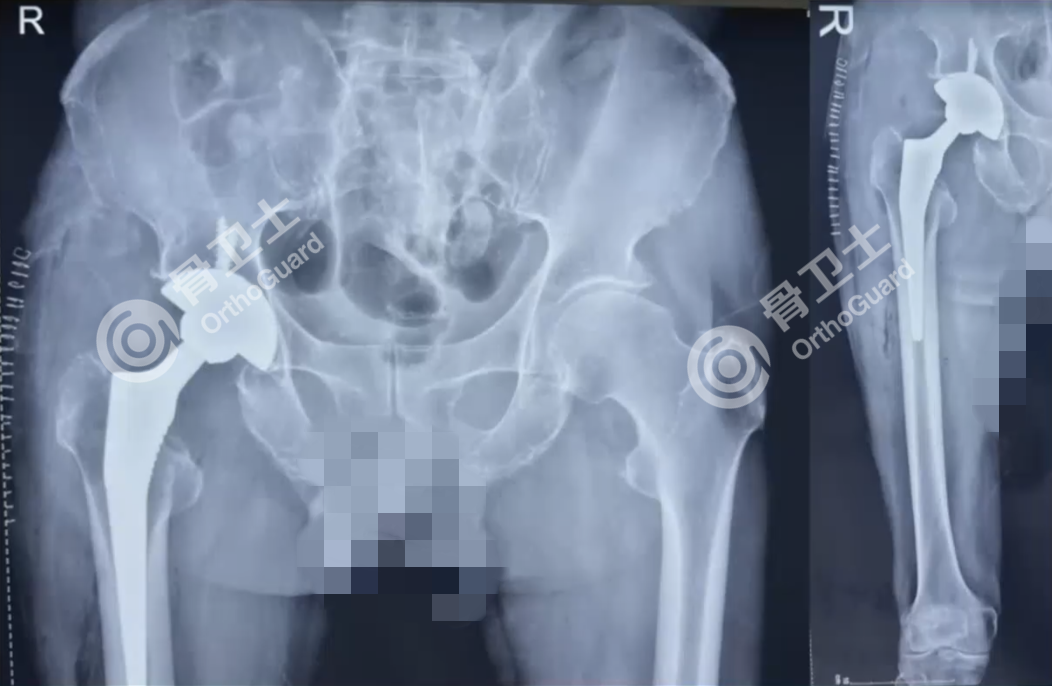

基本情况:男,73岁,因右髋部外伤后疼痛1天入院。

查体:右髋部轻肿胀,腹股沟韧带中点压痛,大粗隆处叩击痛,右下肢纵向叩击痛,髋关节主动活动受限,足趾血运感觉好,踝背伸及跨背伸肌力2级。

既往史:既往“脑血栓”病史12年,“高血压”病史12年,自服药物治疗。

7.png

▲患者术前影像资料

6.png

▲患者术后影像资料

周乙雄教授和陈强副院长就患者手术时机选择及术后发热原因进行讨论。周乙雄教授表示,患者年龄偏大,有脑血栓病史,需检查患者肌力,确认患者髋部肌肉情况,尤其是臀中肌的肌力,这对手术成功与否至关重要。

周乙雄教授强调,手术植入关节假体后,需做髋关节极度屈曲、内收、内旋及屈曲、外展、外旋等动作,以检查髋关节的稳定性,避免脱位发生。肢体长度需在术前有骨盆正位片,测量健侧长度,术中患侧以健侧为准,确定患侧长度,使双下肢等长。

对于不同类型股骨颈骨折的治疗方式,是选择内固定还是关节置换?周乙雄教授指出,一般来讲,年龄在55岁以下的患者,首选内固定,给年轻的病人以愈合的机会;如果年龄偏大,则选择人工关节置换;对于80岁以上的患者,多有一些基础病变,因此首选半髋关节置换,手术快、出血少,术后可以早下地活动,有利于患者恢复,减少合并症。对于该患者术后发烧的原因,周乙雄教授结合患者生活环境(牧羊人),可怀疑是否寄生虫病引起的发热。